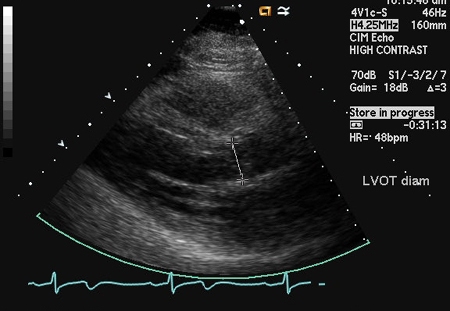

Dopplerfluxometria colorida

Exame

Uma das técnicas mais específicas e sensíveis usadas para julgar a gravidade do fluxo regurgitante, que usa a relação entre a largura do jato proximal e a via de saída do ventrículo esquerdo e a relação entre a área transversal do jato e a via de saída do ventrículo esquerdo. A vena contracta, que é a região mais estreita do jato regurgitante logo abaixo da valva aórtica, também pode ser usada.[24][Figure caption and citation for the preceding image starts]: Incidência do eixo paraesternal longitudinal demonstrando largura e altura de jato de regurgitação aórticaDos acervos Dr. Sanjeev Wasson e Dr. Nishant Kalra; usado com permissão [Citation ends].

[Figure caption and citation for the preceding image starts]: Incidência do eixo paraesternal longitudinal demonstrando o diâmetro da via de saída do ventrículo esquerdoDos acervos Dr. Sanjeev Wasson e Dr. Nishant Kalra; usado com permissão [Citation ends].

[Figure caption and citation for the preceding image starts]: Incidência do eixo paraesternal longitudinal mostrando vena contracta do jato de regurgitação aórticaDos acervos Dr. Sanjeev Wasson e Dr. Nishant Kalra; usado com permissão [Citation ends].

Antigamente era usado o comprimento da coluna de jato no ventrículo, mas esse critério atualmente não é mais considerado uma medida da gravidade.

Incidências paraesternais têm preferência sobre a incidência apical devido à melhor resolução axial.

Resultado

detecção e quantificação do fluxo regurgitante